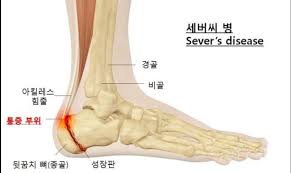

족저근막은 발바닥의 아치 모양 곡선을 유지하고 발에 전해지는 충격을 흡수하는 스펀지 같은 역할로 발바닥 근육을 감싸고 있는 얇은 막입니다. 이곳에 지속적인 충격, 마찰이 전달되면 결국 염증이 생겨 살살 걸어도 발이 아프게 됩니다.

물리적인 자극이 지속될수록 발뒤꿈치뿐 아니라 발 안쪽까지 아프고 쑤시는 증상을 보이기 때문에 가급적 빨리 치료할수록 경과도 좋은 편입니다.